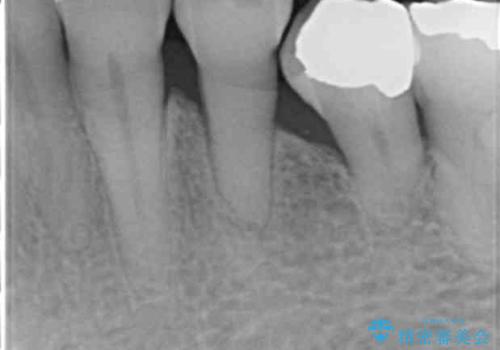

前歯がかけた、ぐらぐらする 60代女性

- 下の前歯が欠けてぐらぐらすることを主訴に来院された患者様です。

4年前に行った他の部位の治療にご満足頂け、再来院して下さいました。(こちらの症例です→ https://seimitsushinbi.jp/case/68066/ )

以前行った奥歯の治療により下顎前歯の動揺は改善傾向にあり顕著ではなかったのですが、欠けて黒くなっていることと少しの動揺が気になるとのことでした。

元気なうちに治療しておきたいという患者様の強いご希望により、下顎前歯の連結補綴と欠けている小臼歯の補綴治療を行いました。